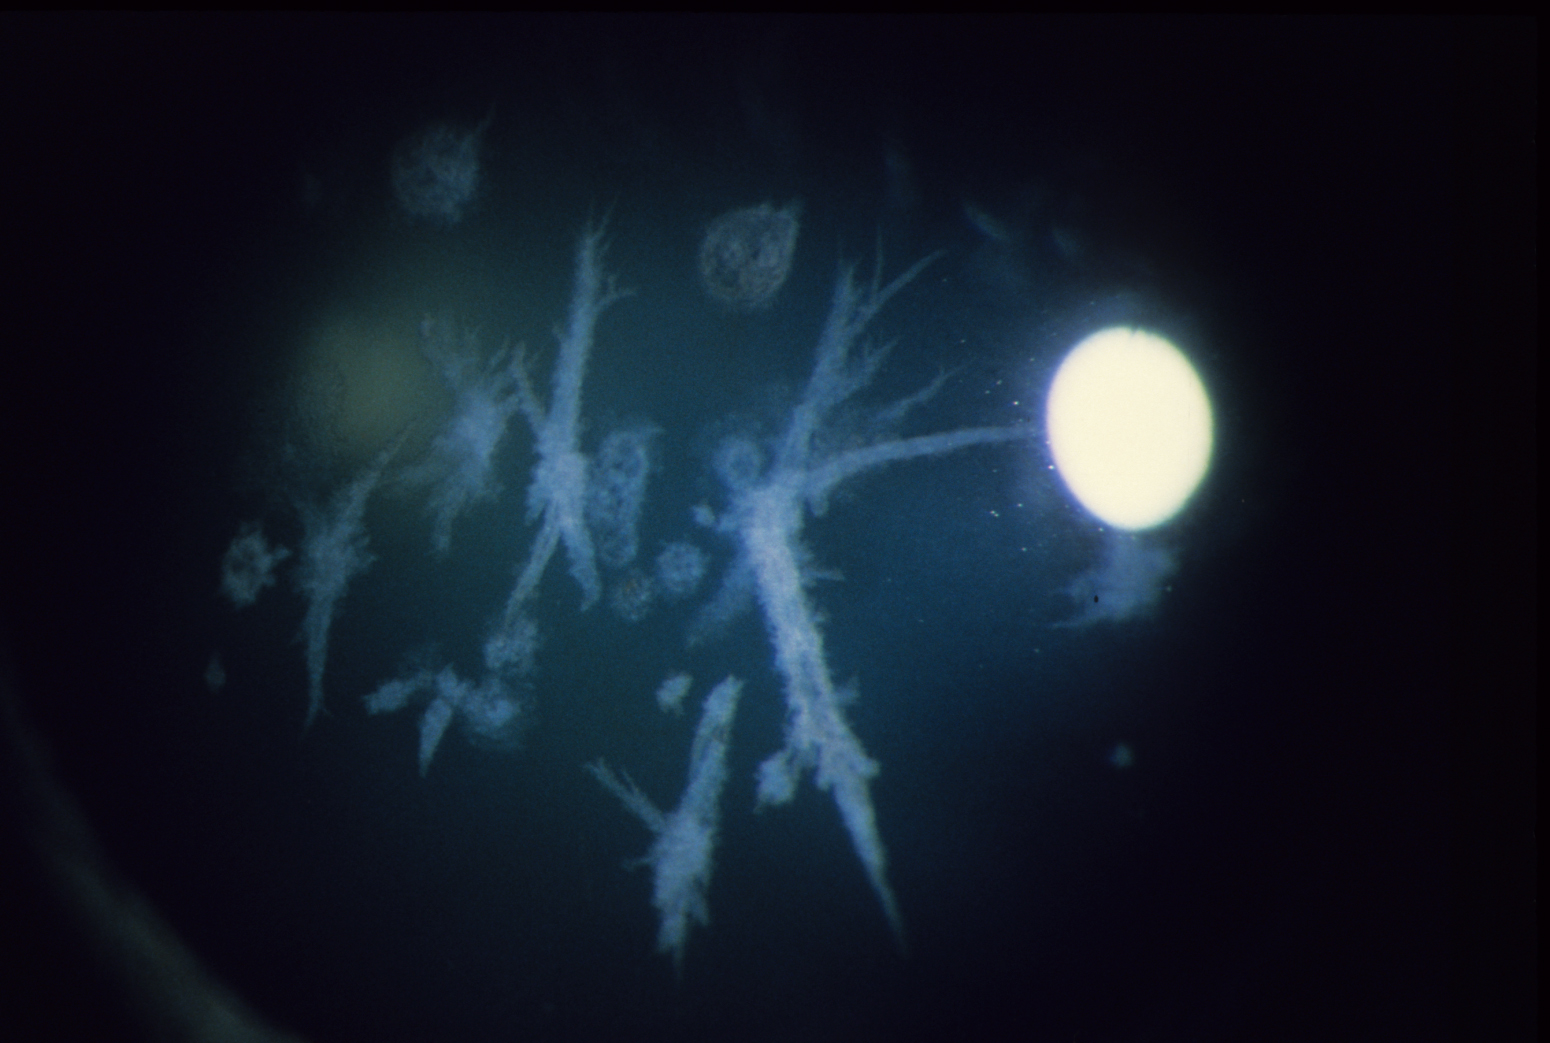

각막 검사에서 각막 중앙에 결정(crystal)이 반짝이는 듯한 모습으로 보이기에 이처럼 이름이 붙여졌습니다.

양측 각막의 중심부 상피하에 콜레스테롤 혹은 다른 지방 성분이 침착되는데,

이모양이 화환 모양의 둥근 형태로 침착되는 형태로 보입니다.

바늘모양의 다색선의 결절이 일정한 방향성 없이

주심부 각막의 보우만층 및 상부기질에서 관찰됩니다.